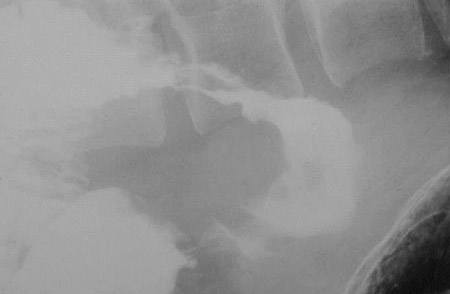

This upper GI series demonstrates an ulceration of the duodenum that appears as an outpouch of contrast into the ulcer base and surrounded by the wall of the ulcer.